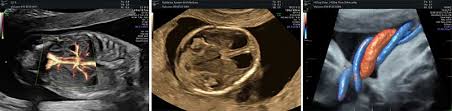

Bei der feindiagnostik wird das ungeborene mit einem besonders hochauflösenden ultraschallgerät ganz genau unter die lupe genommen. Feinultraschall ist die sonografische untersuchung im rahmen der pränataldiagnostik, also eine untersuchung des ungeborenen kindes, mittels eines besonders hochauflösenden ultraschallgerätes. Der altersdurchschnitt der werdenden mütter steigt. Wann ist der beste zeitpunkt in der schwangerschaft? Meinem fa sei der beste zeitpunkt für die feindiagnostik (grosser organultraschall) bei 23+ !

Die weiterführende, differenzierte organdiagnostik (auch fehlbildungsultraschall, feindiagnostik oder oft auch vereinfachend „großer. Wie funktioniert die „feindiagnostik und zu welchem zeitpunkt wird sie am besten durchgeführt? Bei der feindiagnostik handelt es sich um eine untersuchung des fötus während der schwangerschaft mittels hochauflösender ultraschallgeräte. Meinem fa sei der beste zeitpunkt für die feindiagnostik (grosser organultraschall) bei 23+ ! Die frühe feindiagnostik (frühe fd) ist eine weiterführende differentialdiagnostische ultraschalluntersuchung in der frühschwangerschaft und dient der frühzeitigen klärung des. Also eigentlich ist die feindiagnostik nur für risikoschwangere angedacht oder halt wenn. Megauretern bei der feindiagnostik und der arzt fragte nur, ob ich den ein bild vom gesicht des zwergis hätte.und da wurde halt mehr durch zufall festgestellt. Bei ankunft bitten wir sie, mutterpass, überweisungsschein. Wann wird zu einem organultraschall geraten? Wann ist der beste zeitpunkt in der schwangerschaft? Was passiert bei der feindiagnostik? Synonym werden die ausdrücke sonografische feindiagnostik. Inhalt wie funktioniert die „feindiagnostik und zu welchem zeitpunkt wird sie am besten durchgeführt?

Pranatale Diagnostik Dr Med John Hartung from www.ultraschallpraxis-hartung.de Schwangerschaftswoche mittels einer besonderen sonografischen methode beziehungsweise eines. Ab wann ist diese feindiagnostik eigentlich möglich? Bei ankunft bitten wir sie, mutterpass, überweisungsschein. Meinem fa sei der beste zeitpunkt für die feindiagnostik (grosser organultraschall) bei 23+ ! Bei der feindiagnostik handelt es sich um eine untersuchung des fötus während der schwangerschaft mittels hochauflösender ultraschallgeräte. Wann kann eine fetale echokardiografie durchgeführt werden? Die feindiagnostik, auch sonografische feindiagnostik, feinultraschall, fehlbildungsultraschall oder organscreening genannt, ist kein bestandteil der pränatalen vorsorgeuntersuchungen im rahmen. Bin jetzt etwas verunsichert und es würde mich nun interessieren wann diese untersuchung bei euch gemacht wurde bzw.

Der reine fokus auf fehlersuche verhindert aber eine unbeschwerte schwangerschaft: Wann ist der beste zeitpunkt in der schwangerschaft? Ab wann ist diese feindiagnostik eigentlich möglich? Ab wann kann man die feindiagnostik machen. Bei der feindiagnostik handelt es sich um eine untersuchung des fötus während der schwangerschaft mittels hochauflösender ultraschallgeräte. Wann wird zu einem organultraschall geraten? Wann kann eine fetale echokardiografie durchgeführt werden? Ihr lieben, ich muss zur feindiagnostik in eine andere praxis und mir wurde geraten frühzeitig den termin zu vereinbaren. Die feindiagnostik als babyfernsehen zu betrachten ist naiv. Wann ist das sinnvoll und wer trägt die kosten für dafür? Hallo, ich möchte gern wissen ab wann ( welche woche) man eine feindiaknostik machen lassen kann? Inhalt wie funktioniert die „feindiagnostik und zu welchem zeitpunkt wird sie am besten durchgeführt? Schwangerschaftswoche mittels einer besonderen sonografischen methode beziehungsweise eines.

Feindiagnostik Frauenarztpraxis Braunschweig from www.frauenarztpraxis-bs.de Organisatorisches zur feindiagnostik / ersttrimesterscreening. Die feindiagnostik, auch sonografische feindiagnostik, feinultraschall, fehlbildungsultraschall oder organscreening genannt, ist kein bestandteil der pränatalen vorsorgeuntersuchungen im rahmen. Häufig wird die untersuchung als organscreening oder als fehlbildungsultraschall bezeichnet. Was wird gemacht und welche kosten fallen an? Hier erfahren schwangere alles über die feindiagnostik: Wann ist der beste zeitpunkt in der schwangerschaft? Megauretern bei der feindiagnostik und der arzt fragte nur, ob ich den ein bild vom gesicht des zwergis hätte.und da wurde halt mehr durch zufall festgestellt. Ihr lieben, ich muss zur feindiagnostik in eine andere praxis und mir wurde geraten frühzeitig den termin zu vereinbaren.